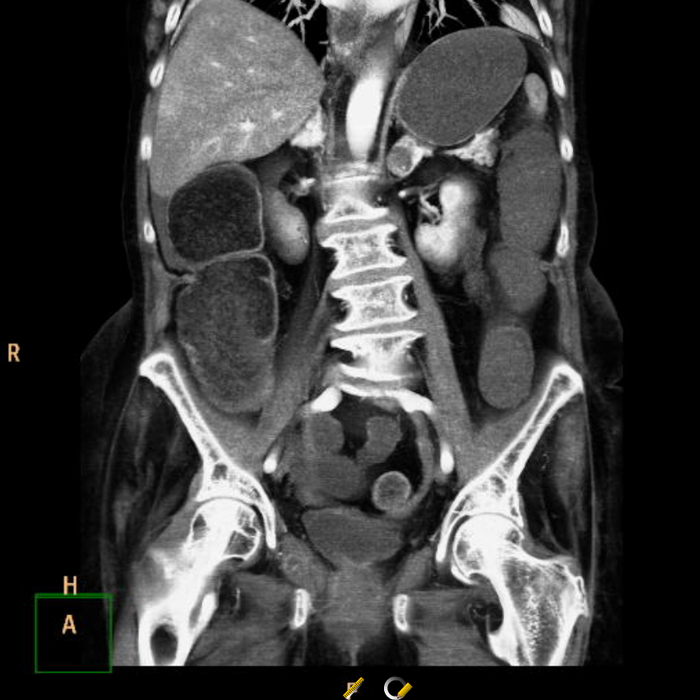

В лёгочном окне - очаги консолидации ("уплотнения" лёгочной ткани) в постеробазальных (задне-нижних) отделах правого лёгкого (на ренгенснимках и КТ, а также МРТ та часть, что на мониторе расположена слева - всегда правая сторона пациента). На последнем снимке серии ниже (сагиттальная или боковая реконтрукция) были непонятные артефакты, как от металла:):

Переключаемся на "костное" окно (позволяет луче оценить кости и прочие плотные структуры), где реально видим "металлический" предмет в просвете правого нижнедолевого бронха: